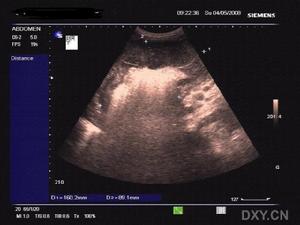

2.功能性腸瘀脹(麻痹性腸梗阻) 主因腸道自主神經系統功能紊亂使消化道蠕動功能失調如全身重症感染、敗血症肺炎腦炎、毒血症或中毒性休克等,引起微循環障礙,胃腸道首先缺血缺氧以致擴張無力而腹脹腹膜炎與腹部損傷(包括手術損傷)後產生腸麻痹氣體吸收障礙亦可引起腹脹特別以結腸脹氣為主,B超檢查、鋇灌腸可見結腸充氣擴張;

3.腹腔積液 腹水引起的腹脹多由於血漿蛋白低下肝硬化,充血性心力衰竭、門靜脈高壓腹腔炎症或腫瘤所致。體徵與脹氣不同,B超檢查X線透視見腸管漂浮在腹水中。

可做B超、鋇灌、腸X線立位照片或透視檢查見小腸內多個液平面及癟縮的結腸,可診為機械性腸梗阻;麻痹性腸梗阻可見結腸充氣擴張;見腸管漂浮在腹水中為腹腔積液特點。

3.B超檢查 B超檢查易於顯示軟組織(如肝脾)、液體(包括腹水)及腎積水、膽總管囊腫等囊性病變。彩色都卜勒可顯示臟器血液供應和脈管系統形態,並可提示血流方向及速度,與CT相比有獨到之處。本項檢查為無創性可以動態觀察或多次,重複檢查且相對價廉,B超檢查目前已經取代了部分常規的放射科檢查,如對於部分先天性肥厚性幽門狹窄的診斷、後尿道瓣膜的定位及腎積水的診斷等。B超檢查也逐漸在急腹症領域開展,如腸套疊與急性闌尾炎的診斷,當然對於任何影像學檢查結果都應該密切結合臨床並相互印證才能不斷提高診斷符合率及套用價值。